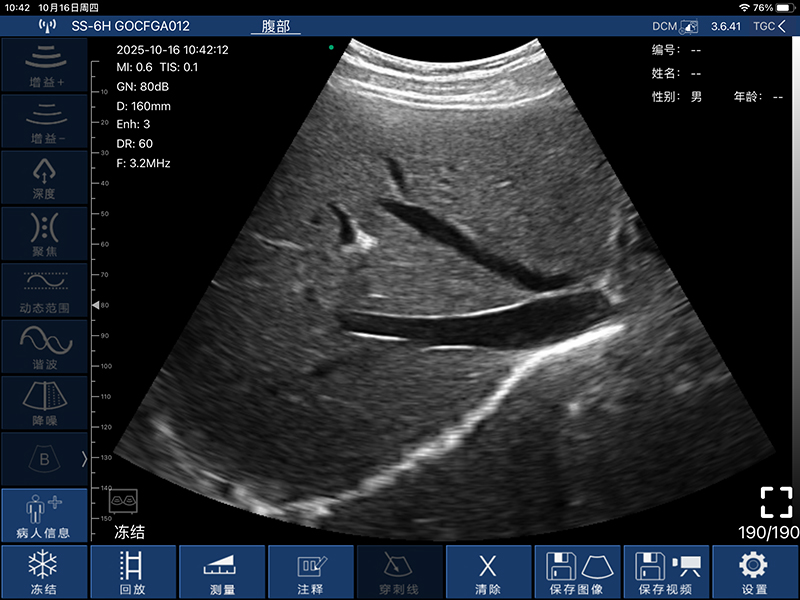

• 扫描方式:电子阵列扫描

• 探头频率:3.2/5.0MHz

• 增益30db-105db

• 扫描深度:90/160/220/305mm,可调

• 显示模式:B、B/M、Color、PW、PDI

• 图像调节:增益、焦点、反相脉冲谐波、降噪

• 穿刺辅助功能:平面内穿刺引导线功能,平面外穿刺引导与血管自动测量功能